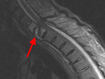

Die meisten Wirbelsäulenerkrankungen, die mit Veränderungen der anatomischen Verhältnisse einhergehen, beruhen auf Verschleiß. Weiter Ursachen können z. B. Unfälle, Tumoren oder Metastasen, Deformitäten, Infektionen oder rheumatische Erkrankungen und angeborene Veränderungen sein. Hier können die Auswirkungen z. B. durch Schädigungen des Rückenmarks oder der Nerven, durch Zerstörung wichtiger stabilisierender Strukturen oder durch eingeschränkte Lebenserwartung erheblich sein. Daher sind häufig größere Operationen erforderlich, die in Abhängigkeit des Schadens nicht immer eine vollständige Wiederherstellung ermöglichen.

Am Zentrum für Wirbelsäulenchirurgie und Schmerztherapie werden sämtliche Erkrankungen und Unfälle der Hals-, Brust- und Lendenwirbelsäule sowie der angrenzenden Strukturen beim Jugendlichen und Erwachsenen diagnostiziert und therapiert.

Schmerzsyndrome der Wirbelsäule; Bandscheibenvorfall; Verschleiß der Bandscheiben; Spinalkanalstenose (Verengung des Wirbelkanals); Instabilitäten; Spondylolisthesis (Wirbelgleiten), Myelopathie (Schädigung des Rückenmarkes); Querschnittslähmung; Erkrankungen bei Kinder und Heranwachsenden (z. B. Formveränderungen, Skoliosen, Kyphosen, angeborene Wachstumsstörungen, Verletzungen, Entzündungen, Tumore und Metastasen); Verletzungen des Rückenmarks; Wirbelkörperbrüche; Deformitäten (Formveränderungen, Skoliose, Kyphose); Tumore und Metastasen; Infektionen; Spondylodiszitis (Infektion von Bandscheiben und Wirbelkörper); rheumatische Instabilitäten der Halswirbelsäule sowie zwischen Kopf und Halswirbelsäule; rheumatische Veränderungen der Brust- und Lendenwirbelsäule (z. B. Morbus Bechterew);Verengungen des Foramen magnum; muskulärer Schiefhals; Syndrome durch die erste Rippe; Deformitäten des Thorax (z. B. Trichterbrust, Kielbrust); Erkrankungen und Verletzungen der Rippen; etc.